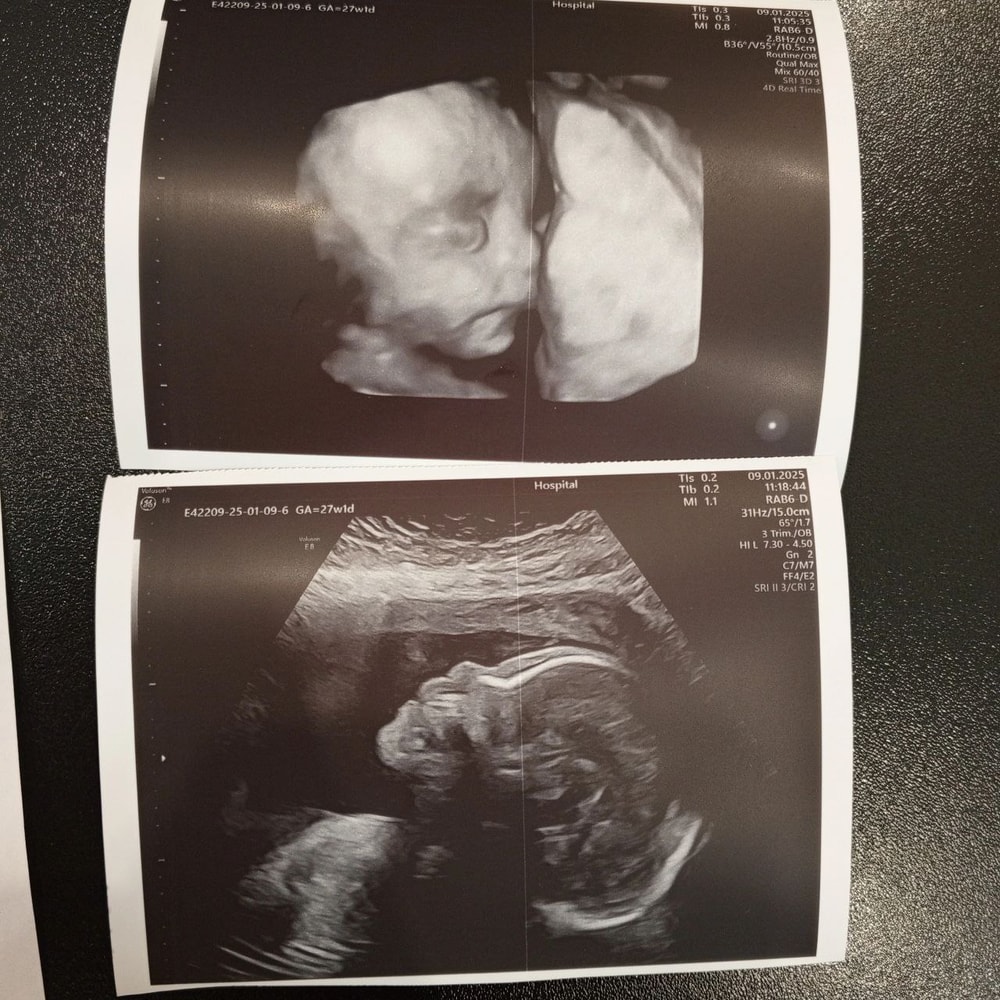

Дочка с ногами у лица, щекой на плаценте, другой щекой на ручке. Один нос торчит!) Но был момент, когда ручку убрала она от лица и картинка сложилась:))) Ничего особо не увидели( Надо было раньше ехать(( Но посмотрели все органы, каждый орган! Все на месте, все хорошо, лишнего ничего не выросло!)

РОСТ 37СМ

ВЕС 1150Г

Соответствует 28.2 неделям)) У меня 27.4)